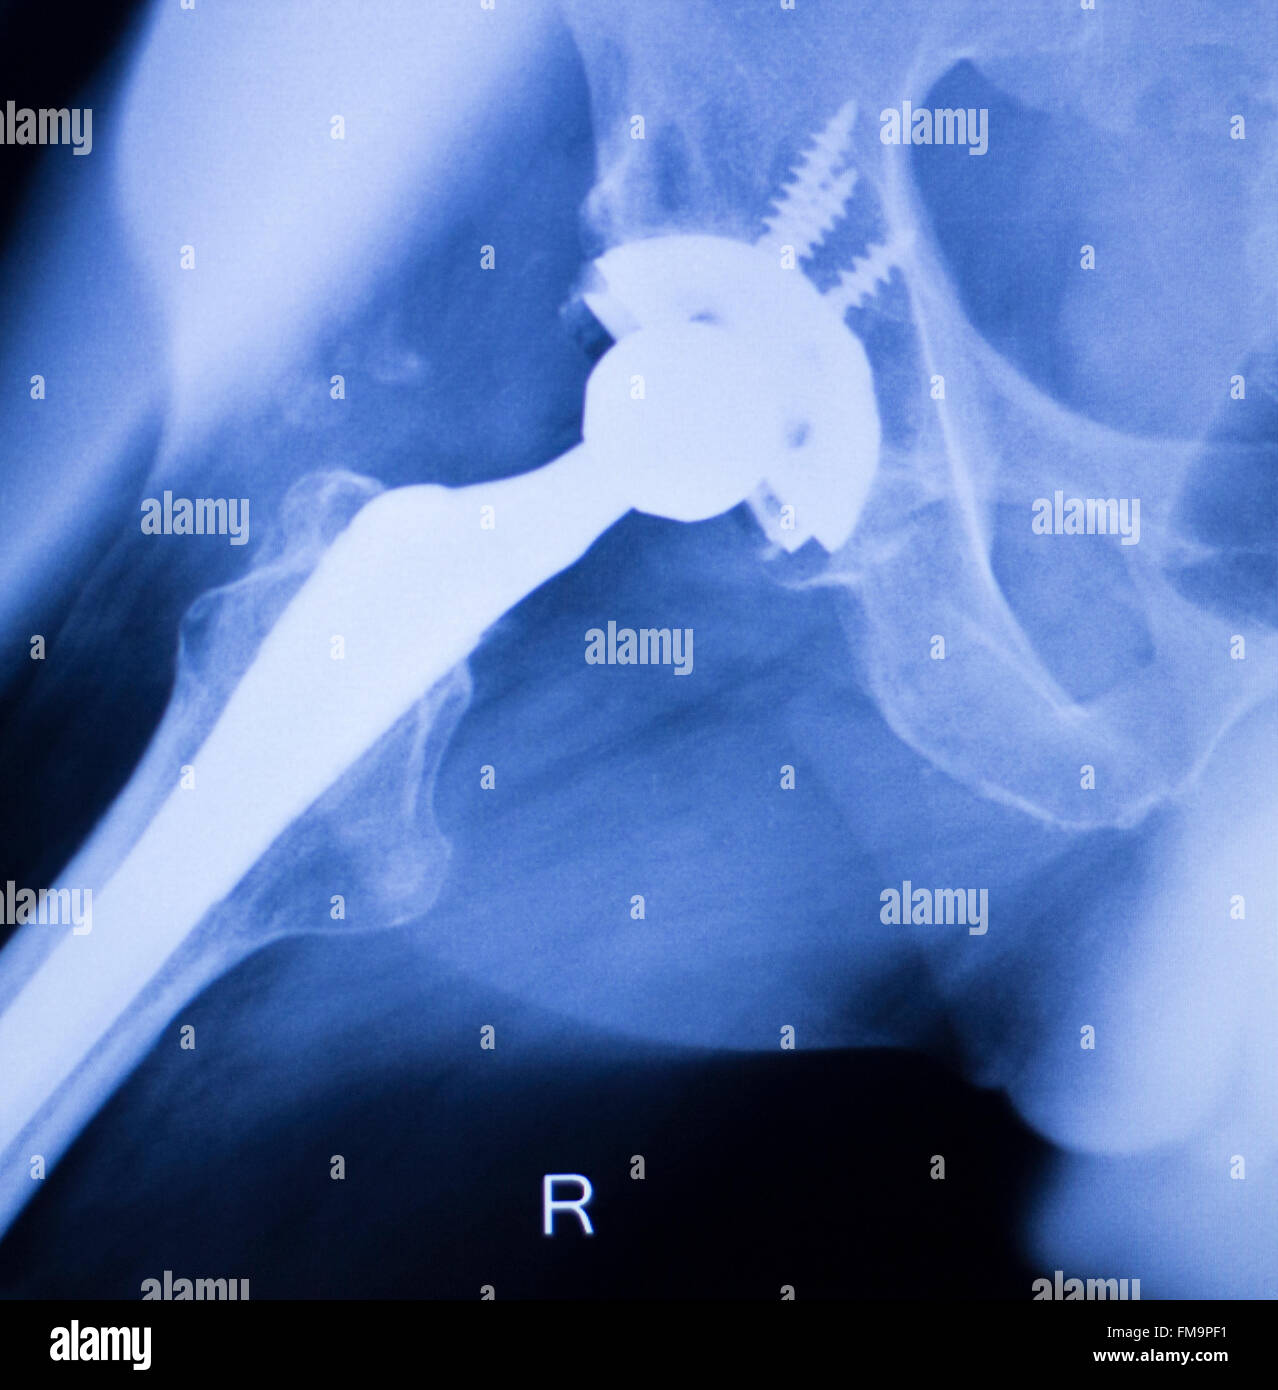

From www.dreamstime.com

Hip Joint Xray Test Scan Stock Photos Free & RoyaltyFree Stock Hip Replacement Test if you're considering hip replacement surgery, here are some things that can help you decide if it's right for you. hip replacement can address hip pain and stiffness for people with arthritis, avascular necrosis or other forms of hip joint damage. The socket is formed by the acetabulum,. During a hip replacement surgery, an orthopaedic surgeon replaces both. Hip Replacement Test.

From www.alamy.com

Hip replacement xray orthopedic medical xray Traumatology test scan Hip Replacement Test During a hip replacement surgery, an orthopaedic surgeon replaces both ends or one end of the damaged hip joint with artificial parts. hip replacement surgery is a procedure in which a doctor surgically removes a painful hip joint and replaces. a total hip replacement is a procedure where a surgeon replaces the ball and socket of your hip. Hip Replacement Test.

Hip replacement xray orthopedic medical xray Traumatology test scan Hip Replacement Test hip replacement can address hip pain and stiffness for people with arthritis, avascular necrosis or other forms of hip joint damage. The hip is one of the body's largest joints. your provider might recommend a hip replacement if pain and other symptoms in your hip affect your. if you're considering hip replacement surgery, here are some things. Hip Replacement Test.